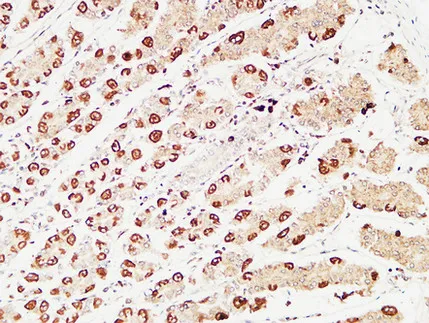

pS2 Rabbit Polyclonal Antibody

Cat: APRab16574